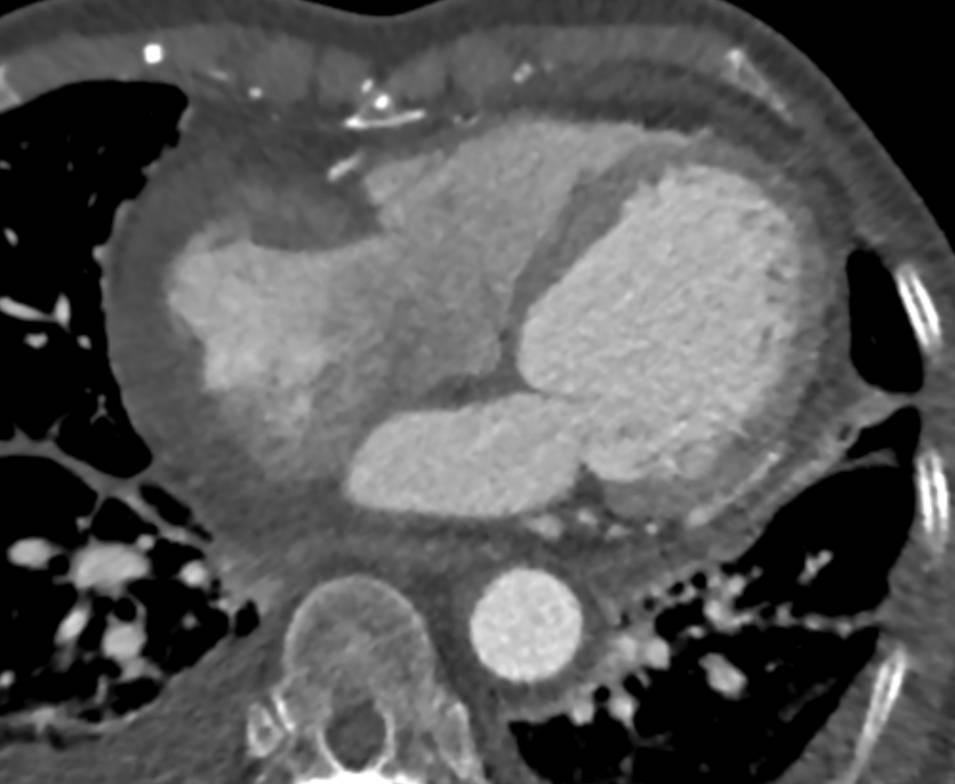

F/73, Incidentally found right atrial mass on echocardiography for evaluation of orthopedic surgery. Previous pulmonary tuberculosis (+), DM (-), HTN (-)

Hwanseok Yong, Korea University Guro Hospital